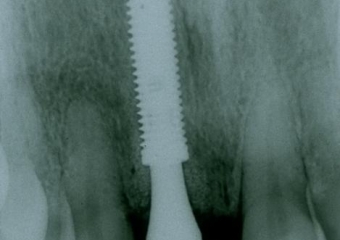

Implante instalado imediatamente após extração